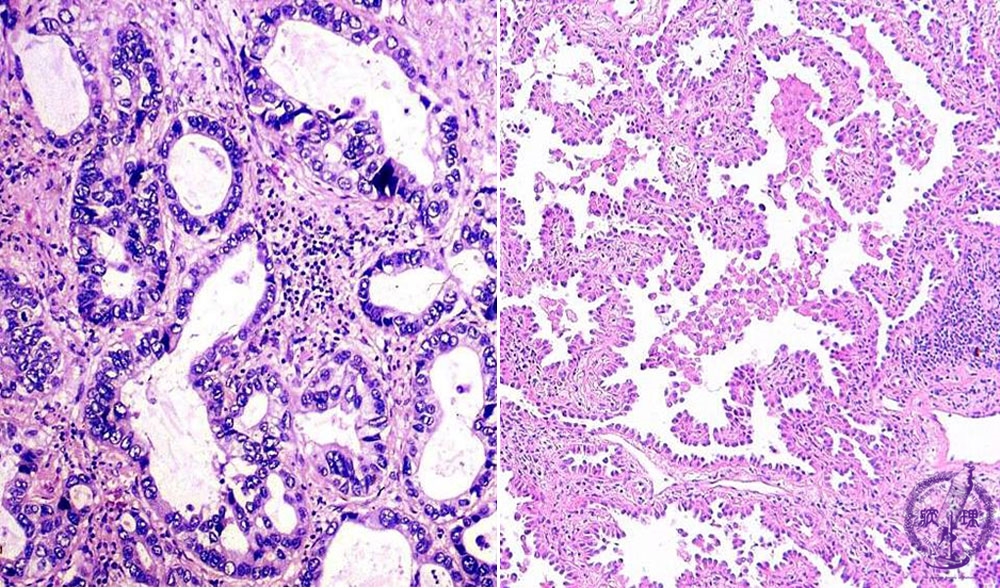

Microscopic view (HE stain, Left: High power view, Right: intermediate power view): Adenocarcinoma of lung. Tubular (left) or papillary (right) structure is sometimes prominent.